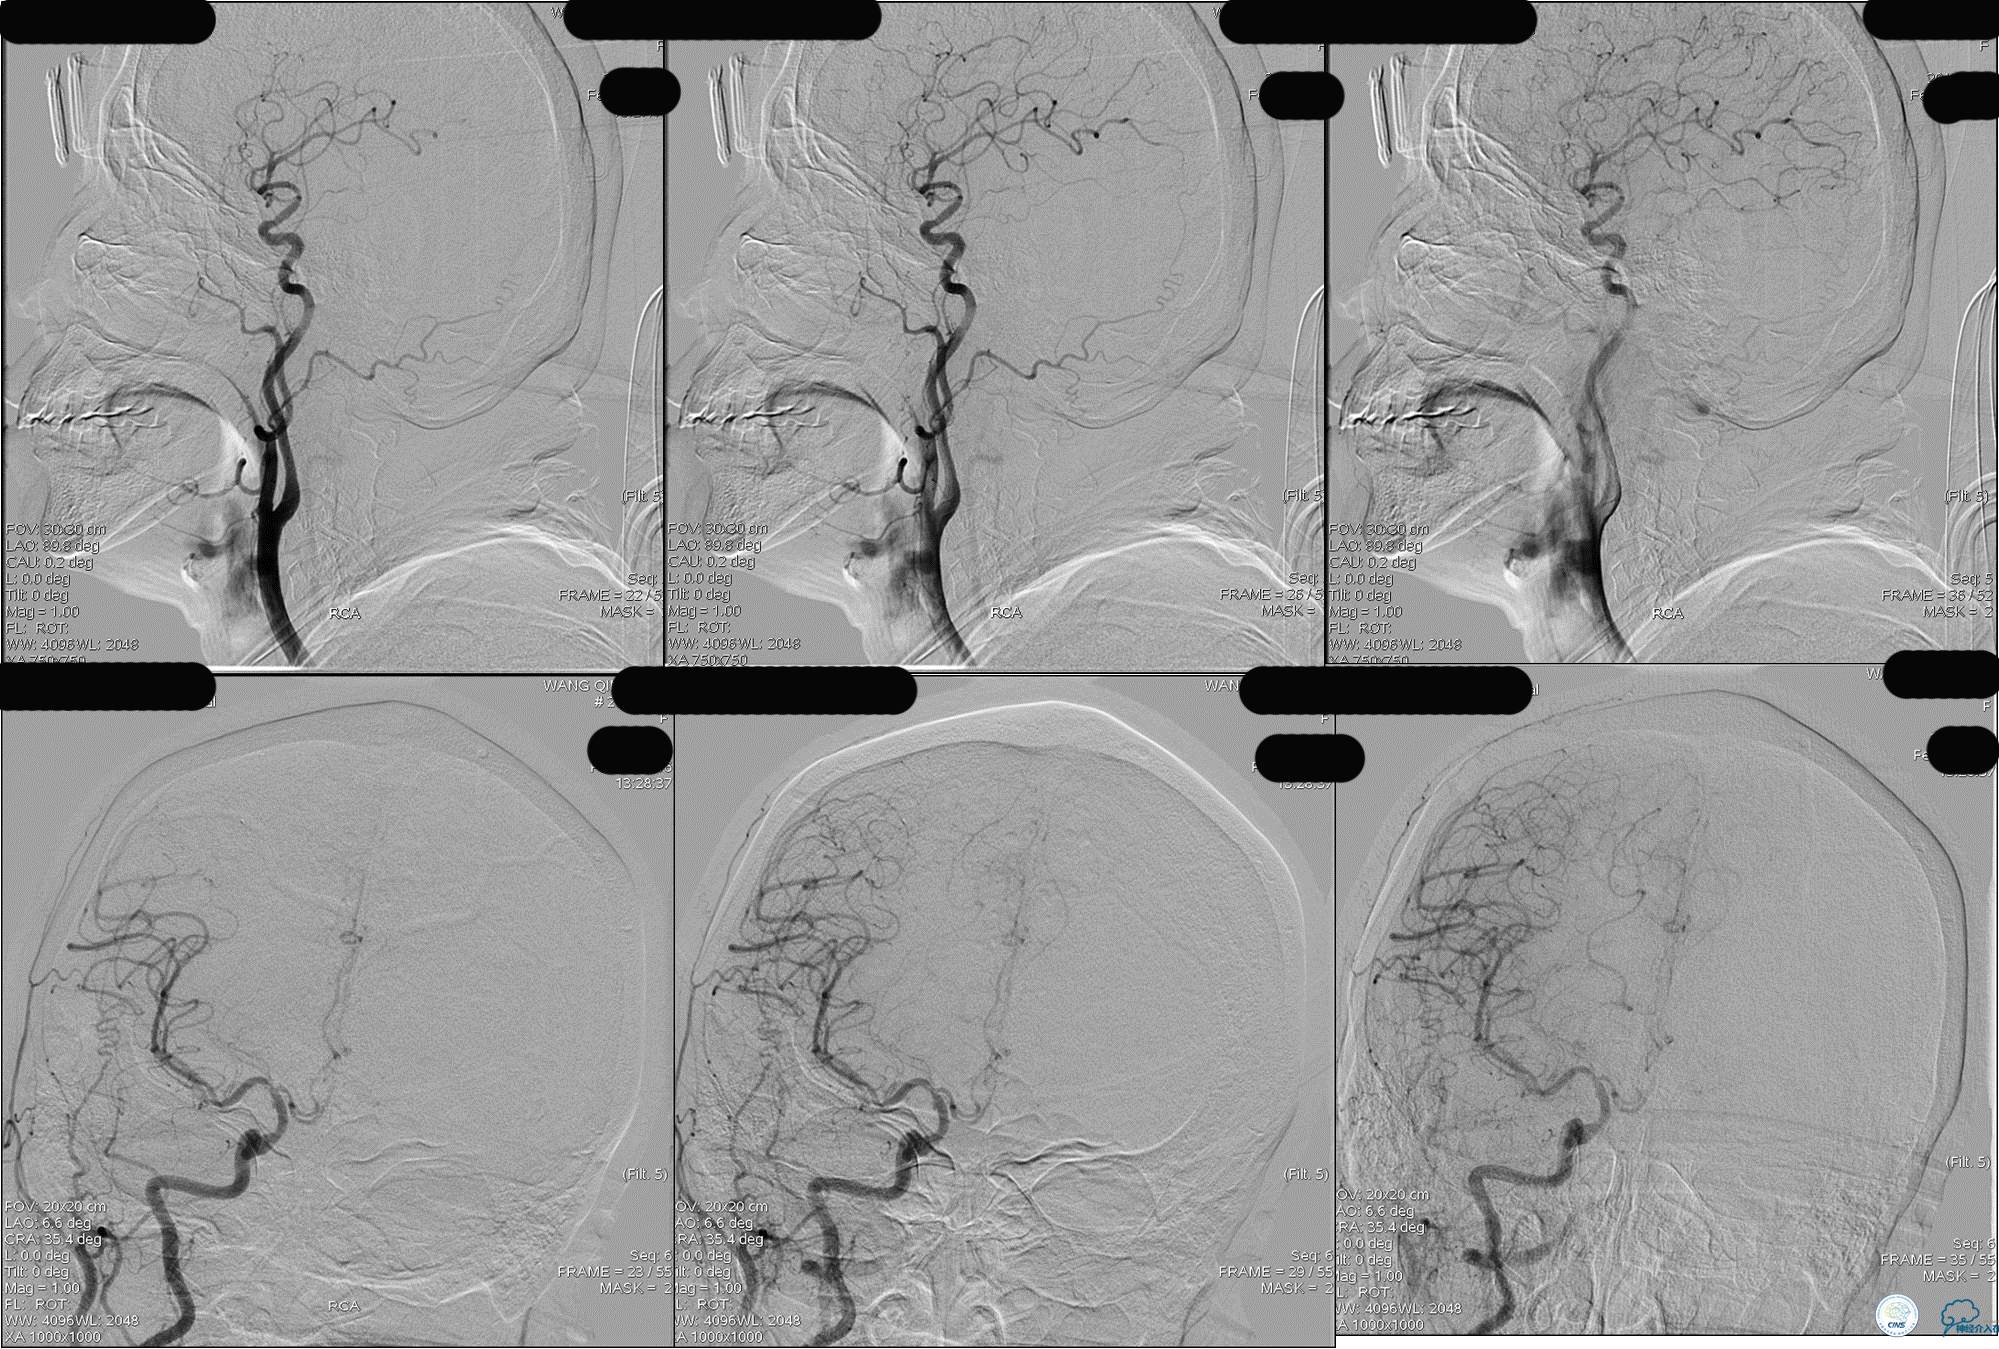

》DSA资料(左侧颈动脉)

》DSA资料(右侧颈动脉)

》DSA资料(左侧椎动脉)

》DSA资料(右侧椎动脉)